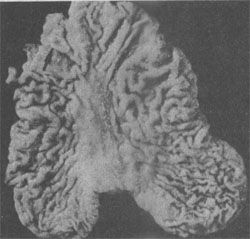

图10-14 息肉型胃癌

肿块呈息肉状突起于胃腔内